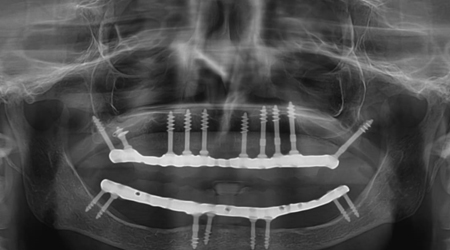

Dental Implant Packages (Lower Jaw)

Technique INR US

8 implants + 14 units Metal-free bridge (Zirconia) 350000 5400

8 implants + 14 units Ceramic bridge (Porcelain fused to metal) 300,000 4500

Dental Implant Packages (Upper Jaw)

10-12 implants including 2 Pterygoid implants + 14 units Metal-free bridge (ZIRCONIA) 400,000 6200

10 implants including 2 Pterygoid implants + 14 units Ceramic bridge (Porcelain fused to metal) 350,000 5500

Full Mouth Rehabilitation with 6-8 Implants Protocol for good bone

Upper Jaw/Lower Jaw (Per Jaw)- NOBEL BIOCARE

6-8 NOBLE BIOCARE Implants + 12 to 14 Units Metal Ceramic Bridge (Porcelain Fused to Metal 350000 5400

6-8 NOBLE BIOCARE Implants + 12 to 14 Units ZIRCONIUM (Metal Free) CERAMIC BRIDGE 500000 7600